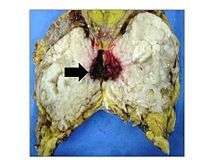

Classification

Phyllodes tumors are a fibroepithelial tumor composed of an epithelial and a cellular stromal component. They may be considered benign, borderline, or malignant depending on histologic features including stromal cellularity, infiltration at the tumor's edge, and mitotic activity.[1] All forms of phyllodes tumors are regarded as having malignant potential. A large series from the M.D. Anderson Cancer Centre reported the incidence of each as benign (58%), borderline (12%), and malignant (30%). Malignant phyllodes tumours behave like sarcomas and can develop blood-borne metastases. Approximately 10% of patients with phyllodes tumours develop distant metastases and this can go up to 20% in patients with histologically malignant tumours.[2] The commonest sites for distant metastases are the lung, bone, and abdominal viscera. Rare sites of metastasis like to parotid region have also been described.[3]